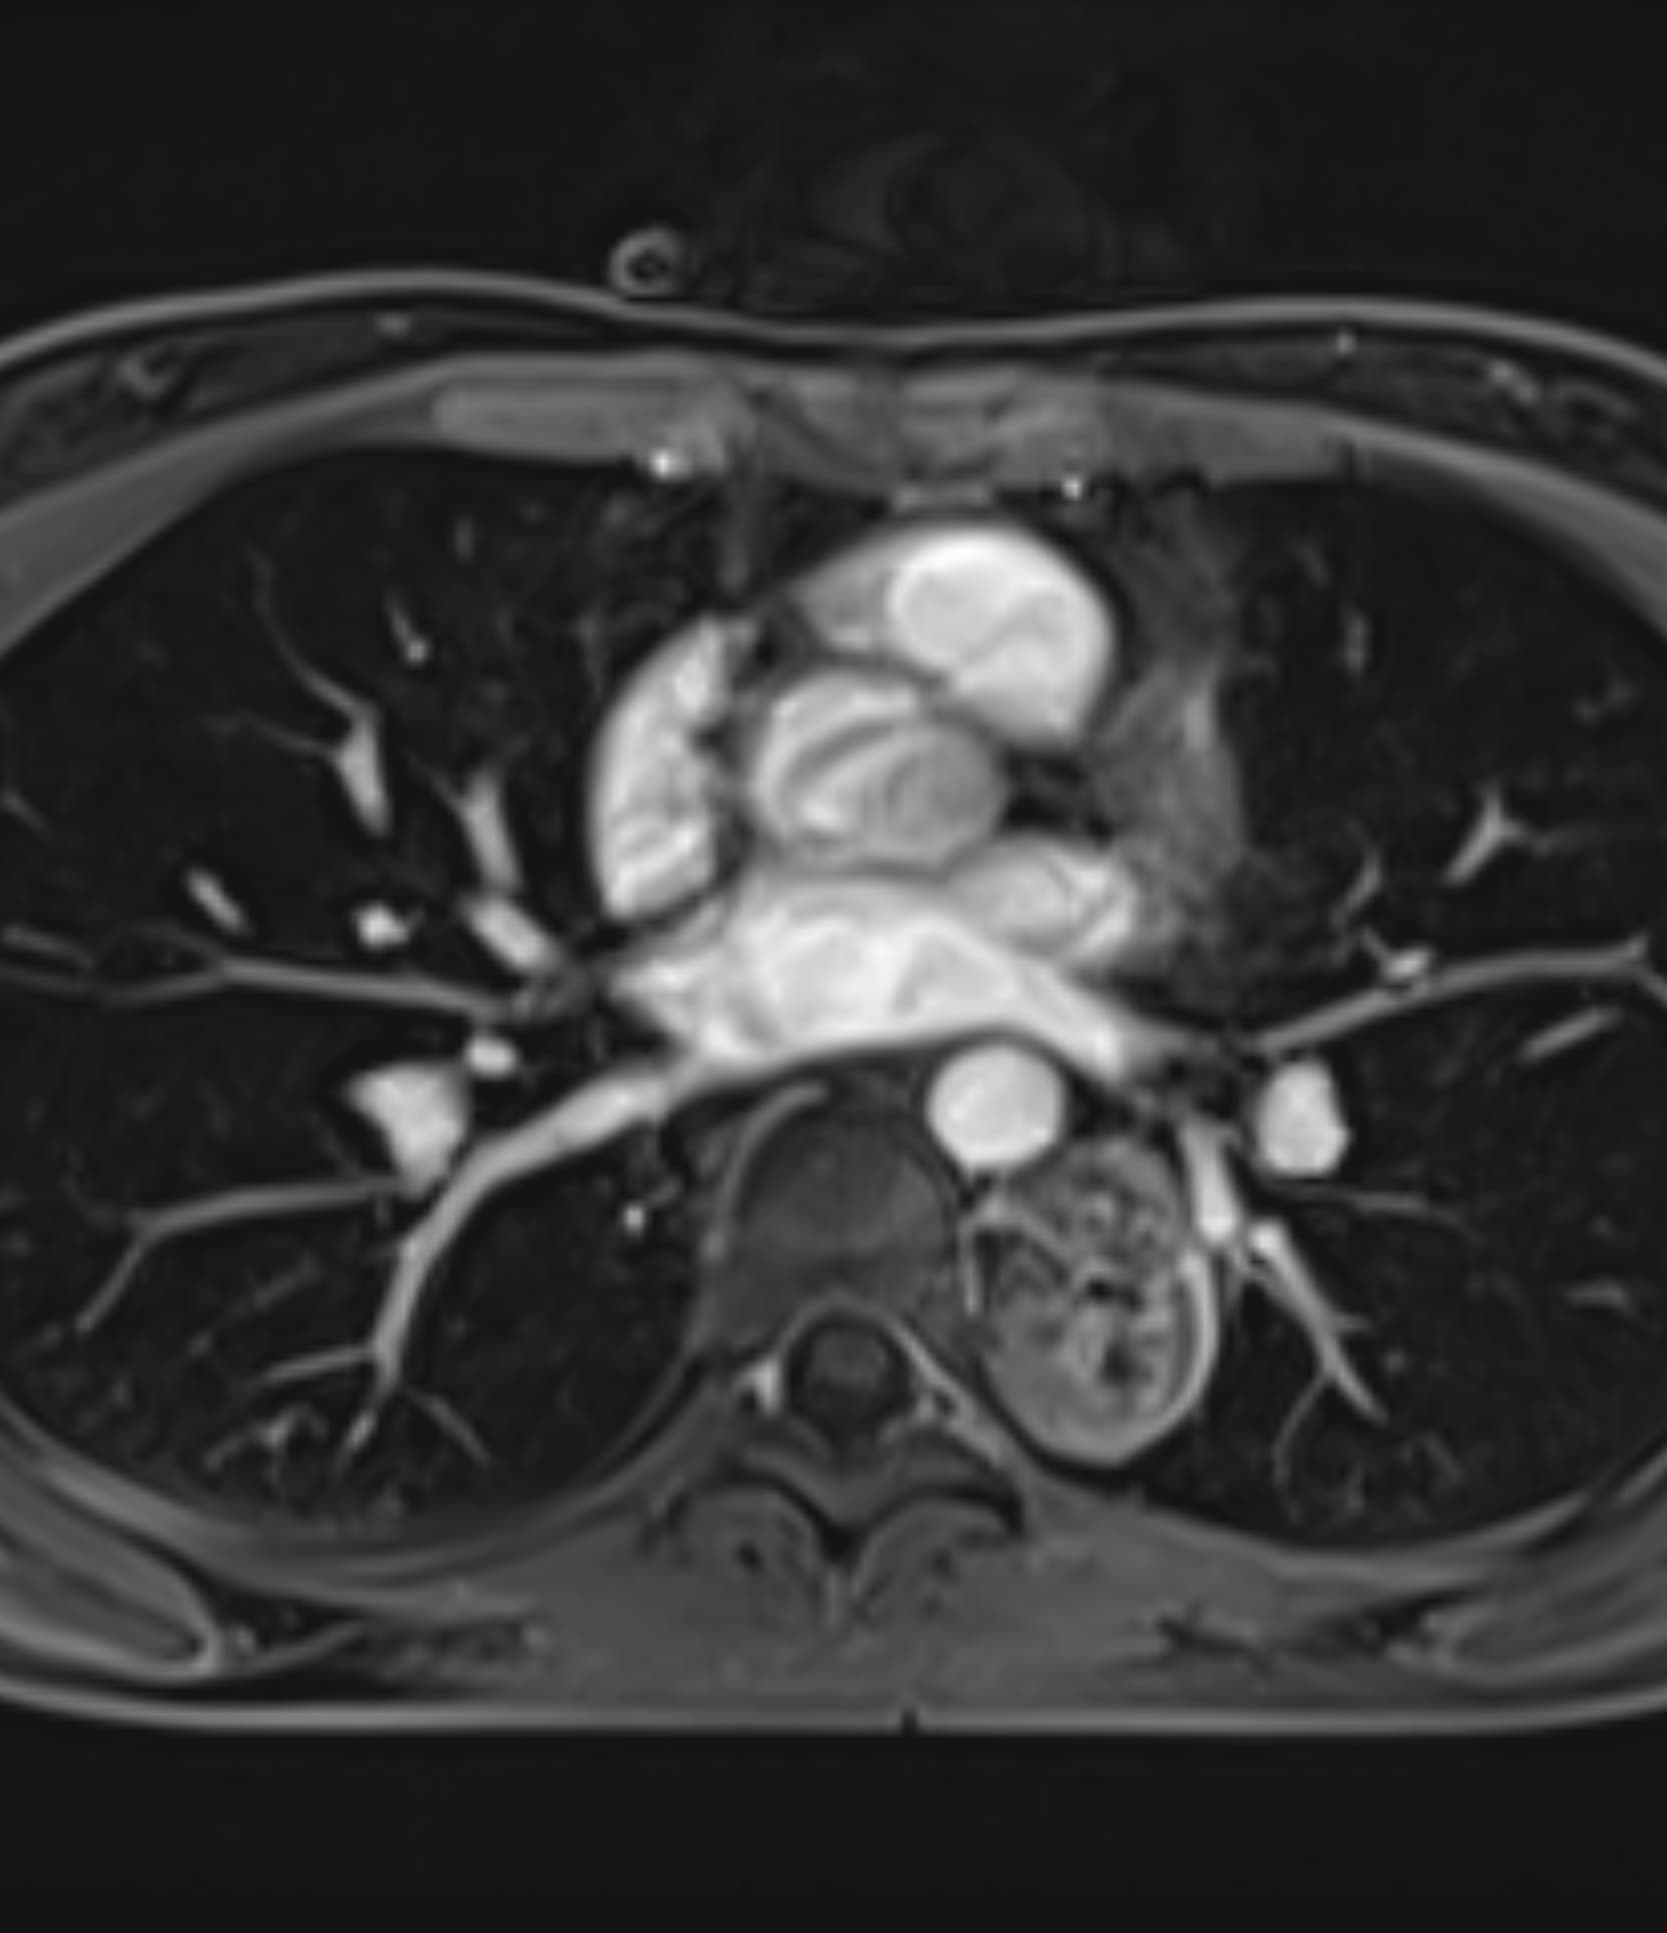

Δείτε πραγματικά παραδείγματα του SwiftMR™ σε διάφορα συστήματα MRI και ανατομικές περιοχές

Scan time 03:08

Scan time 1:12